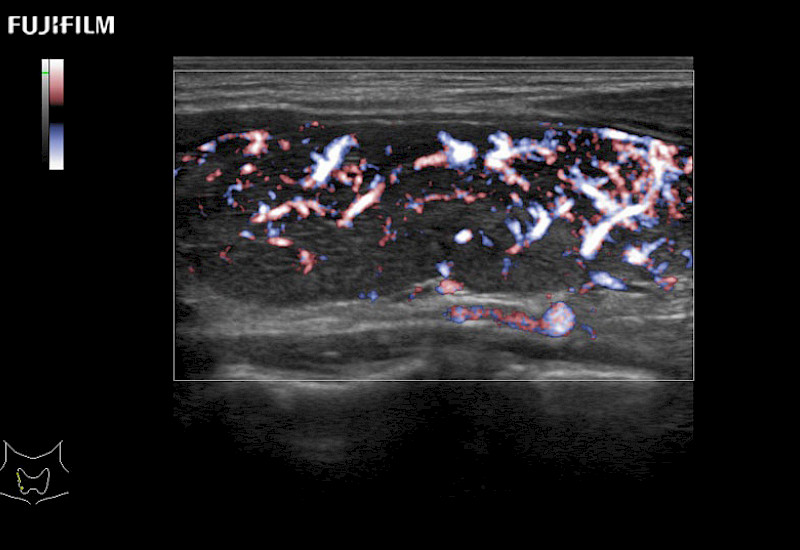

Fujifilm Healthcare understands that Surgical Oncologists demand excellence in their operating rooms — from their staff and the equipment they depend on. Fujifilm Healthcare's dedication to Surgical Oncologists provides outstanding ultrasound technology, professional support and the specialized tools necessary to best perform comprehensive real-time ultrasound imaging.

For precise surgical oncology ultrasound imaging, Fujifilm Healthcare offers premium level solutions that include:

Our dedication to Surgical Oncology allows us to offer superior image quality, outstanding system reliability and intuitive use of cutting edge technology.

The ARIETTA 750 incorporates all of the proven technologies and functions that medical professionals have come to expect from Fujifilm Healthcare.

ARIETTA 750 is the definitive diagnostic ultrasound solution for any clinical setting - Private Office, Imaging Center, or Hospital. The ARIETTA platform provides the ultimate in clinical performance with its state-of-the-art features and large user-friendly display.